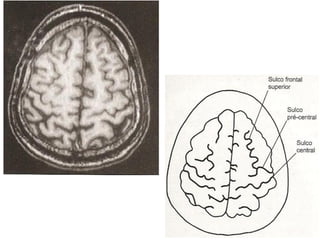

Ressonância Magnética do Crânio

• Sistema de obtenção de

imagens é mais sensível à

natureza molecular dos tecidos;

• Alta densidade tissular não

resulta em resolução de

contraste.

   Doenças da substância branca;

   Neoplasias;

   Doenças infecciosas;

   Distúrbios hemorrágicos;

   Distúrbios isquêmicos.

Sulco       Sulco

pré-central   central